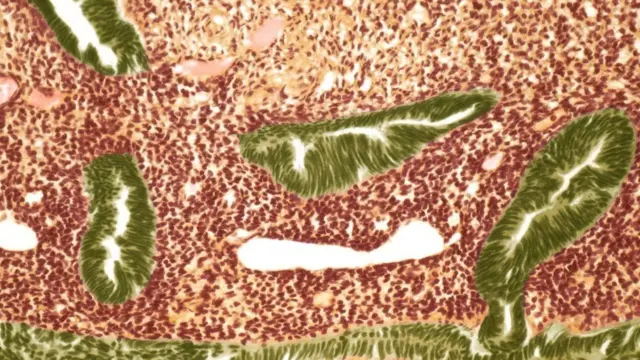

Xigashada Sawirka, STEVE GSCHMEISSNER/SCIENCE PHOTO LIBRARY